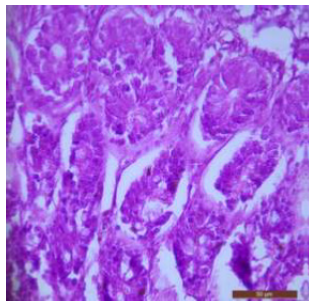

The duodenum of control rat showed histological features such as presence of different layers such as mucosa, submucosa, muscularis and serosa. The lining of epithelium of microvilli was composed of many cell types such as goblet cells, Paneth cells and absorptive columnar epithelial cells (Figure 1). Brünner’s glands were seen in the submucosal region of the duodenum which secrete alkaline fluid containing mucin (Figure 2). The rats treated with 600mg/kg b.w./day for 40 days revealed thickened and scattered villi (Figure 3). Hypertrophy of goblet cells and damaged crypts were also observed. (Figure 4). The necrotic Brünner’s gland showed inflammation and dilation of spaces (Figure 5).

Figure 1: T.S. of duodenum of control rat showing crypts (↑), closely packed microvilli (↑), well developed submucosa and muscularis externa. H&E × 100.